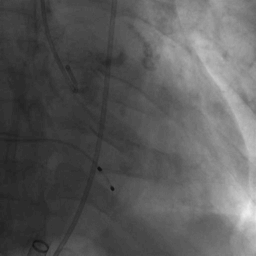

瓣膜释放过程

瓣膜释放完毕